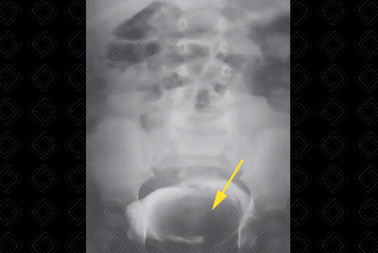

Texto alternativo para a imagem Figura 3. Créditos: Dra. Elazir Mota - Rio de Janeiro/RJ

Descrição das figuras 3 e 4: Ureterocele no assoalho vesical à esquerda (seta vermelha). Na foto de baixo, observamos que ela está relacionada à duplicidade pieloureteral completa, com pólo superior do rim esquerdo displásico.

• Ultrassonografia do aparelho urinário: Imagem arredondada, anecoica, sem fluxo ao Doppler colorido na topografia do óstio ureterovesical acometido, melhor avaliada na fase de enchimento vesical. Atenção! Quando a bexiga estiver muito repleta, a ureterocele pode estar colabada e não ser visualizada (figuras 1, 3 e 4);